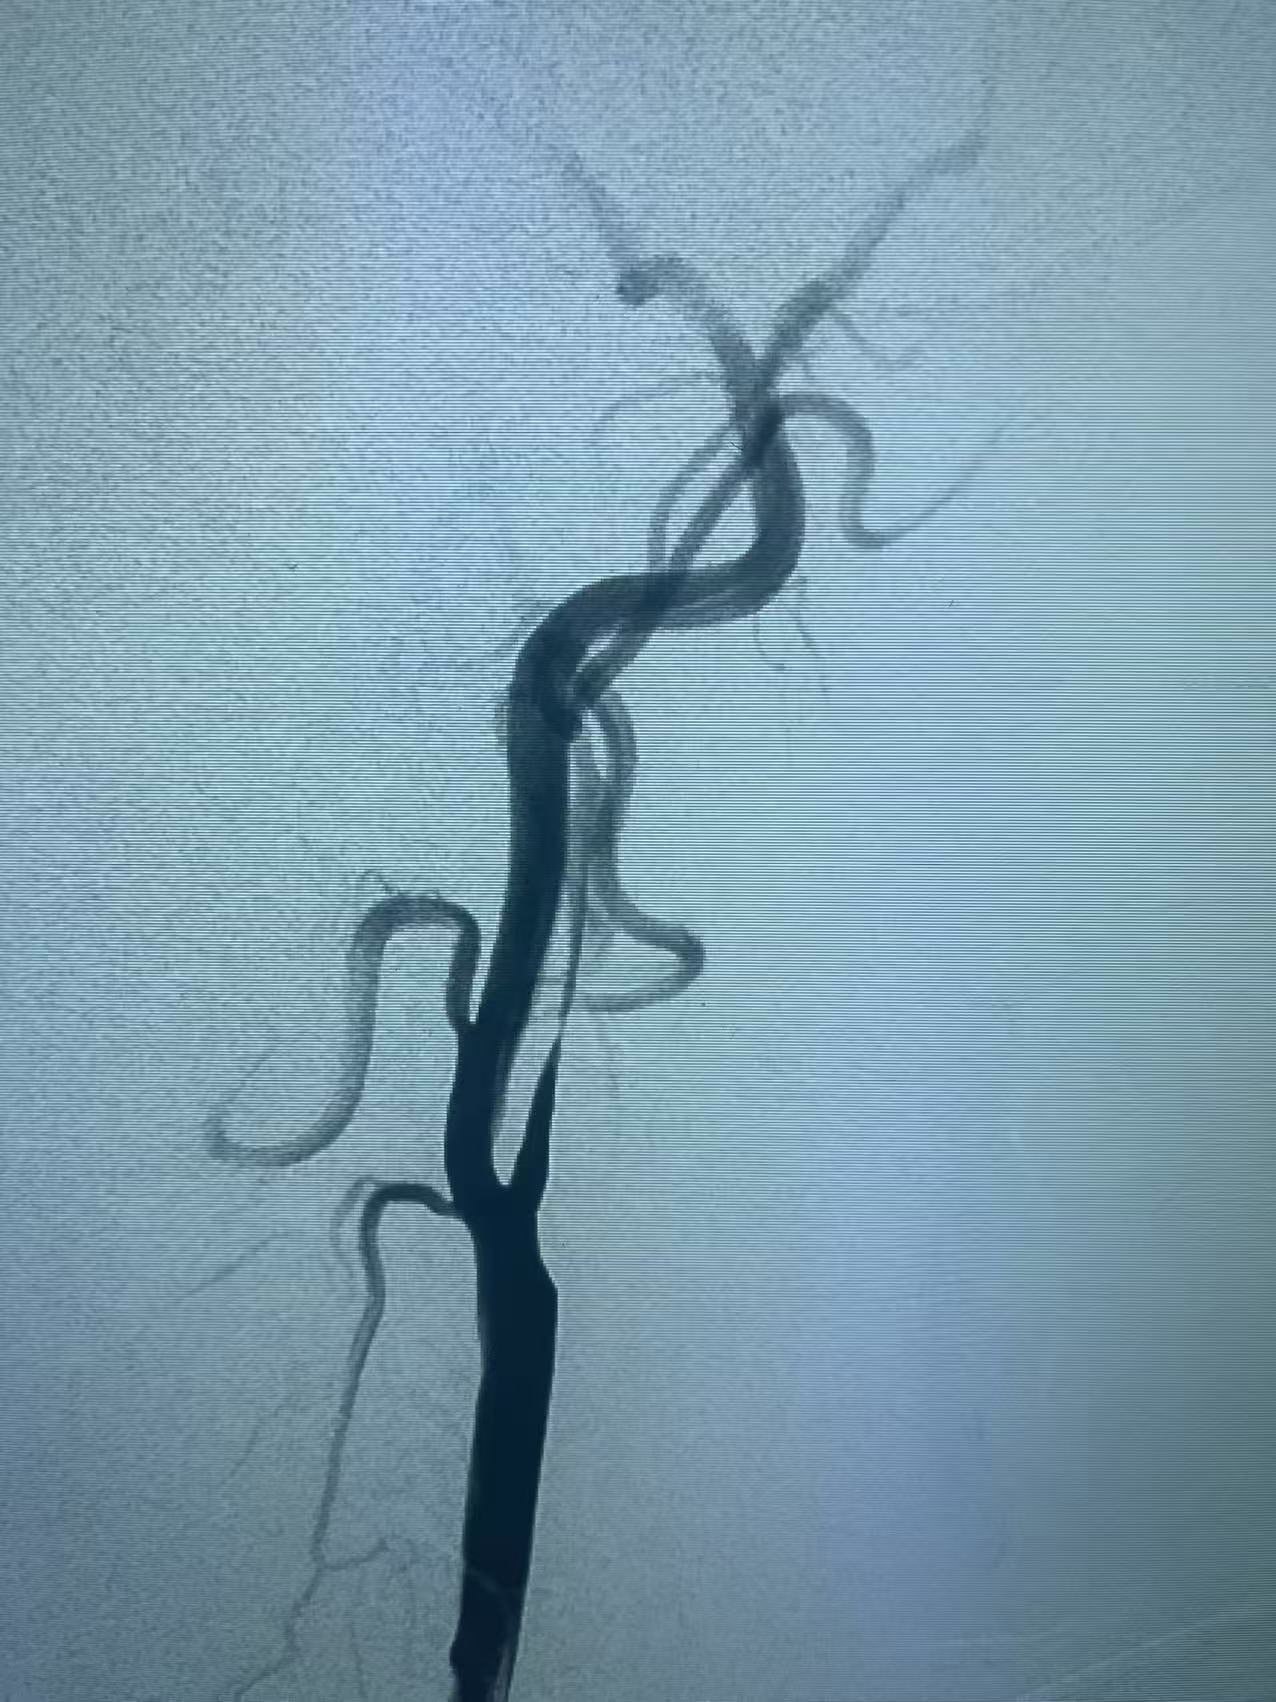

颈内动脉开口重度狭窄基础之上的急性闭塞